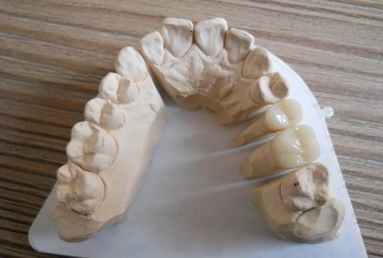

Full ceramic crowns on upper second premolar and first upper molar